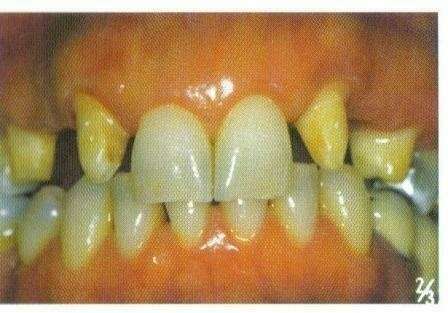

Guérison parodontale. Réalisé à Auriol, proche Aubagne

Les maladies parodontales sont des infections des tissus parodontaux (gencives et os sous-jacent) qui soutiennent les dents. Leur traitement repose principalement sur un protocole de nettoyage et de désinfection.

Ces maladies également appelées parodontites (ou déchaussements des dents) touchent environ 80% de la population adulte occidentale, ce qui en fait la maladie chronique la plus fréquente. En outre, près de 15% des personnes qui en souffrent sont atteintes de formes sévères de la maladie.